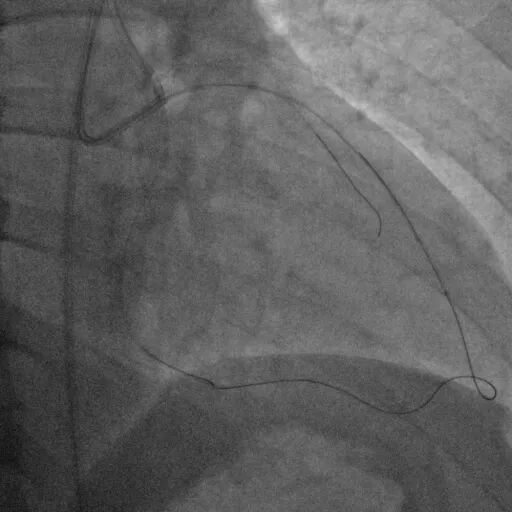

Corsair135辅助下先后尝试使用P200/G3导丝未能突破近端纤维帽,最终CP12突破后进入血管结构内,同时进行多角度确认。

尝试调整导丝重回真腔未成功,直接使用XTA导丝knuckle。

跟进corsair并交换LP球囊后,先后尝试G3/CP12/8-20等导丝穿刺均失败。

直接尝试逆向,RCA中段3.0*10切割后,使用Finecross150+SUOH03通过心外膜逆向进入LAD,FC轻松跟进。